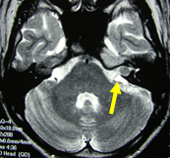

●聴神経腫瘍

耳の奥の内耳と脳を結ぶ神経に良性腫瘍が発生することがあります。良性腫瘍であるために転移したりすることはありませんが、大きくなると難聴が進み、更に耳鳴りふらつきめまいが出るようになります。腫瘍の発育は通常はゆっくりしていますが脳を圧迫するようになると、様々な症状がでるようになります。